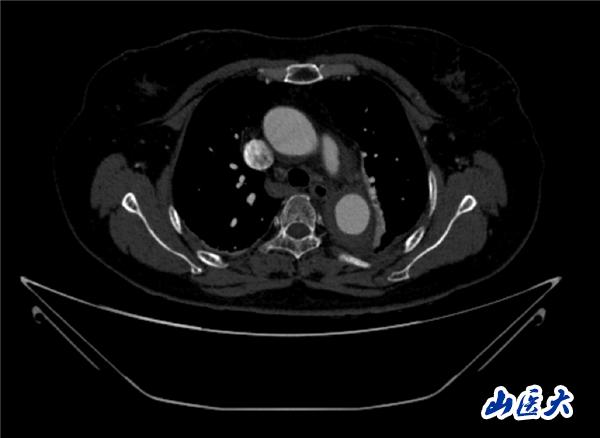

首例患者是一位55歲的女性,她患有高血壓約2年時(shí)間,平時(shí)也會(huì)規(guī)律服用多種降壓藥,但血壓控制始終不盡人意。2023年4月下午,她出現(xiàn)不明原因的頭痛,在家拔罐緩解少許便未到醫(yī)院就醫(yī),次日凌晨突感胸悶、胸背疼痛伴有呼吸困難等癥狀、家人急忙撥打了120,把患者送入醫(yī)院急診科進(jìn)行救治,醫(yī)生在急診科行胸腹主動(dòng)脈CTA時(shí),顯示主動(dòng)脈弓部-降主動(dòng)脈及腹主動(dòng)脈壁間血腫,遂收治入醫(yī)院血管外科,患者入院10天后復(fù)查血腫仍未有改善,依然伴有胸背部疼痛等不適,如不進(jìn)一步處理,可能發(fā)展為夾層危及生命,患者及家屬經(jīng)過(guò)與醫(yī)生團(tuán)隊(duì)了解溝通,決定進(jìn)行創(chuàng)傷小、恢復(fù)快的介入手術(shù)治療。張瑋教授、符偉國(guó)教授、董紅霖教授及其血管外科團(tuán)隊(duì)(閆盛、常文凱、田琴琴)共同商討手術(shù)方案,最終確定使用Zipper?一體式主動(dòng)脈弓覆膜支架系統(tǒng),行胸主動(dòng)脈覆膜支架腔內(nèi)隔絕術(shù)+無(wú)名動(dòng)脈、左頸總動(dòng)脈、左鎖骨下動(dòng)脈分支重建術(shù)為患者進(jìn)行治療。董紅霖教授及其血管外科團(tuán)隊(duì)根據(jù)患者術(shù)前頭顱CT平掃提示雙側(cè)側(cè)腦室旁缺血灶,血壓控制不穩(wěn)定,屬夾層壁間血腫非典型夾層等風(fēng)險(xiǎn)點(diǎn),制定了完整的手術(shù)方案,術(shù)中經(jīng)股動(dòng)脈置入Zipper支架主體,經(jīng)預(yù)留導(dǎo)絲超選無(wú)名動(dòng)脈,并確保主體支架對(duì)位準(zhǔn)確,順利置入左頸總動(dòng)脈、左鎖骨下動(dòng)脈支架,重建弓上三分支。手術(shù)過(guò)程非常順利。術(shù)后觀察主動(dòng)脈及分支覆膜支架定位準(zhǔn)確;無(wú)內(nèi)漏;分支支架通暢,動(dòng)脈供血正常。

術(shù)前CTA